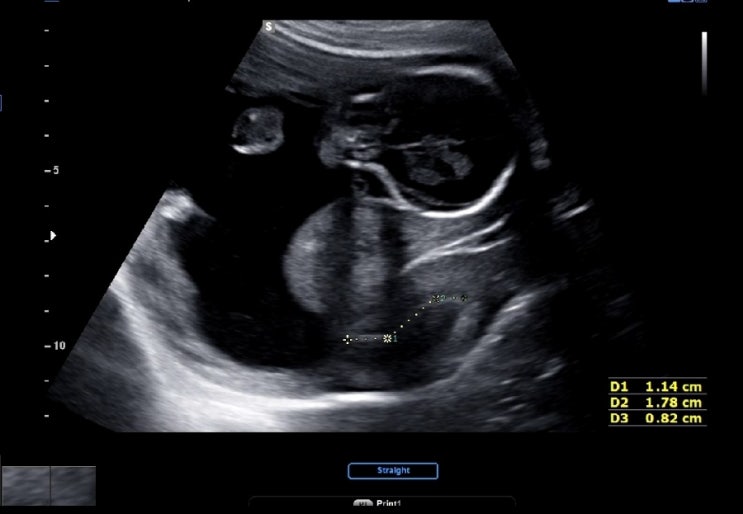

임신 23주 5일 초음파, 경부길이

2023.08.17. 세브란스 다녀온 지 벌써 2주! 지난번에도 경부길이가 조금 짧게 나왔기 때문에, 경부길이랑 ...